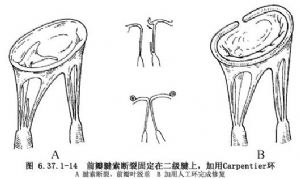

①腱索断裂:后瓣腱索断裂,受累的瓣叶<后瓣的1/3者可矩形切除瓣叶,边缘缝合,对应的瓣环做折叠(图6.37.1-12),也可用瓣叶滑行方法(图6.37.1-13)。前瓣腱索断裂,常用的方法有:一级腱索断裂,将瓣叶边缘固定在二级腱索上(图6.37.1-14)。此方法要有1或2根较厚和结实的第2级腱索。先在断裂的腱索上缝2或3针,然后缝至二级腱索上打结;腱索移植用于前瓣腱索断裂,把与之相对应的带腱索的后瓣切下,乳头肌劈开,将切下的后瓣固定在前瓣叶上。后瓣叶对缘缝合,瓣环折叠(图6.37.1-15);三角形切除,在腱索断裂的瓣叶处做窄的等边三角形切除,通常不超过1.5cm。